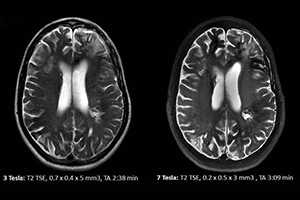

يحتوي Star-Test ، الذي يقدم خدمة التشخيص في إسطنبول منذ عام 1993 ، على أكثر الأجهزة الإشعاعية تقدمًا مع التكنولوجيا.